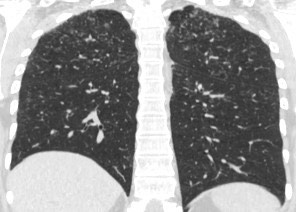

1947. У пациентки 17 лет при выполнении компьютерной томографии легких определяются многочисленные мелкие очаги 1 — 4 мм, в корнях легких визуализируются многочисленные увеличенные бронхопульмональные лимфатические узлы до 16 мм, рентгенологическая картина соответствует